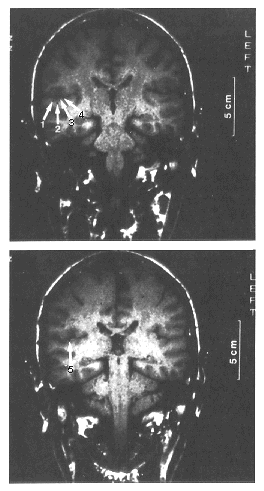

FIG. 6

Coronal MRI tomogram of the subject whose data are presented in Figure 5. Locations of the current dipoles are marked by black dots at the tips of the arrows. From Pantev et al. (50).